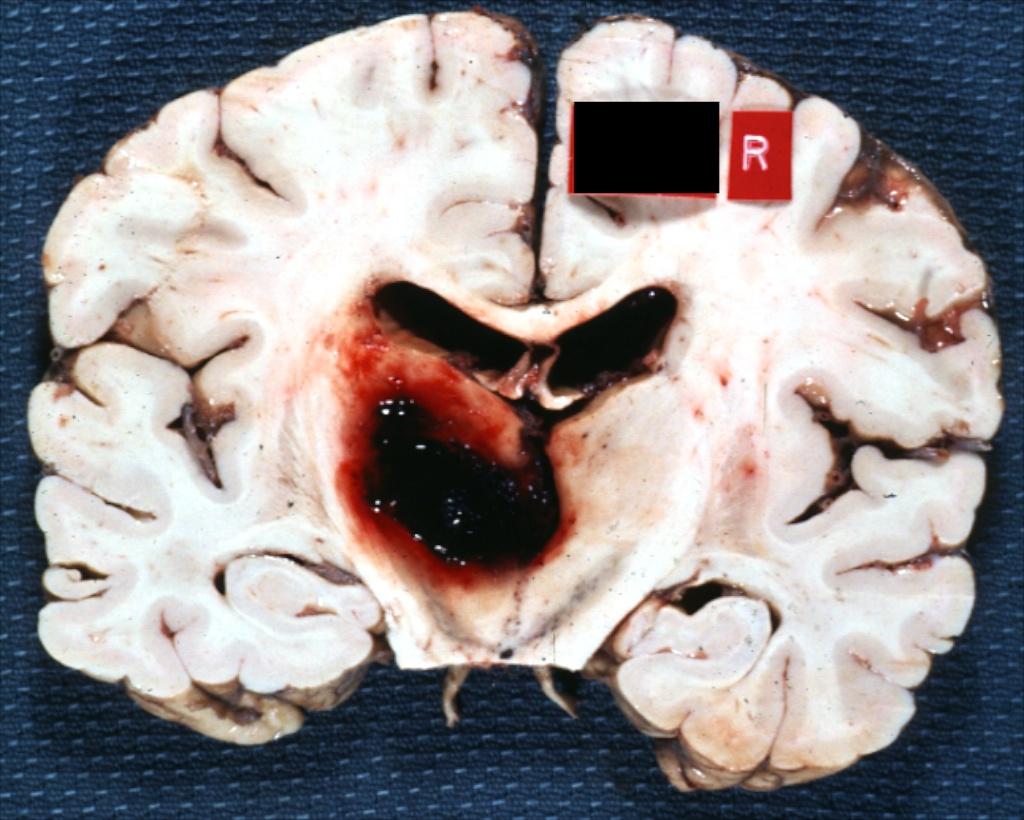

Pathology